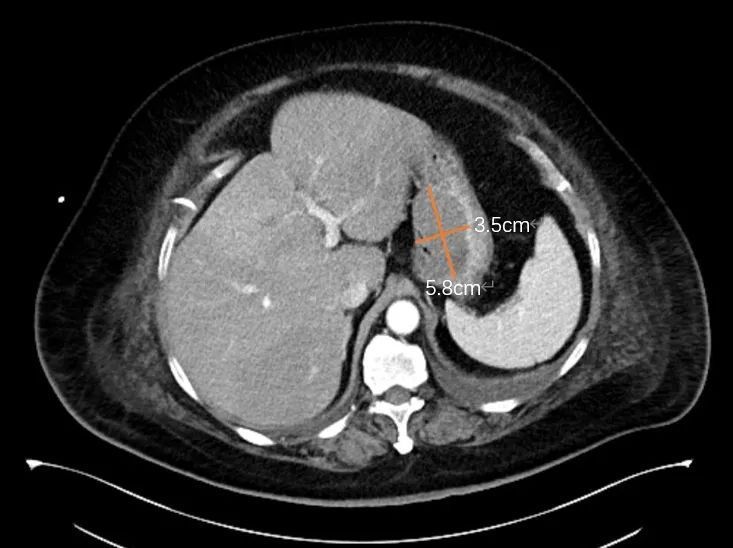

意外发现胃贲门部

有一个5.8cm×3.5cm的肿块

考虑为间质瘤或平滑肌瘤